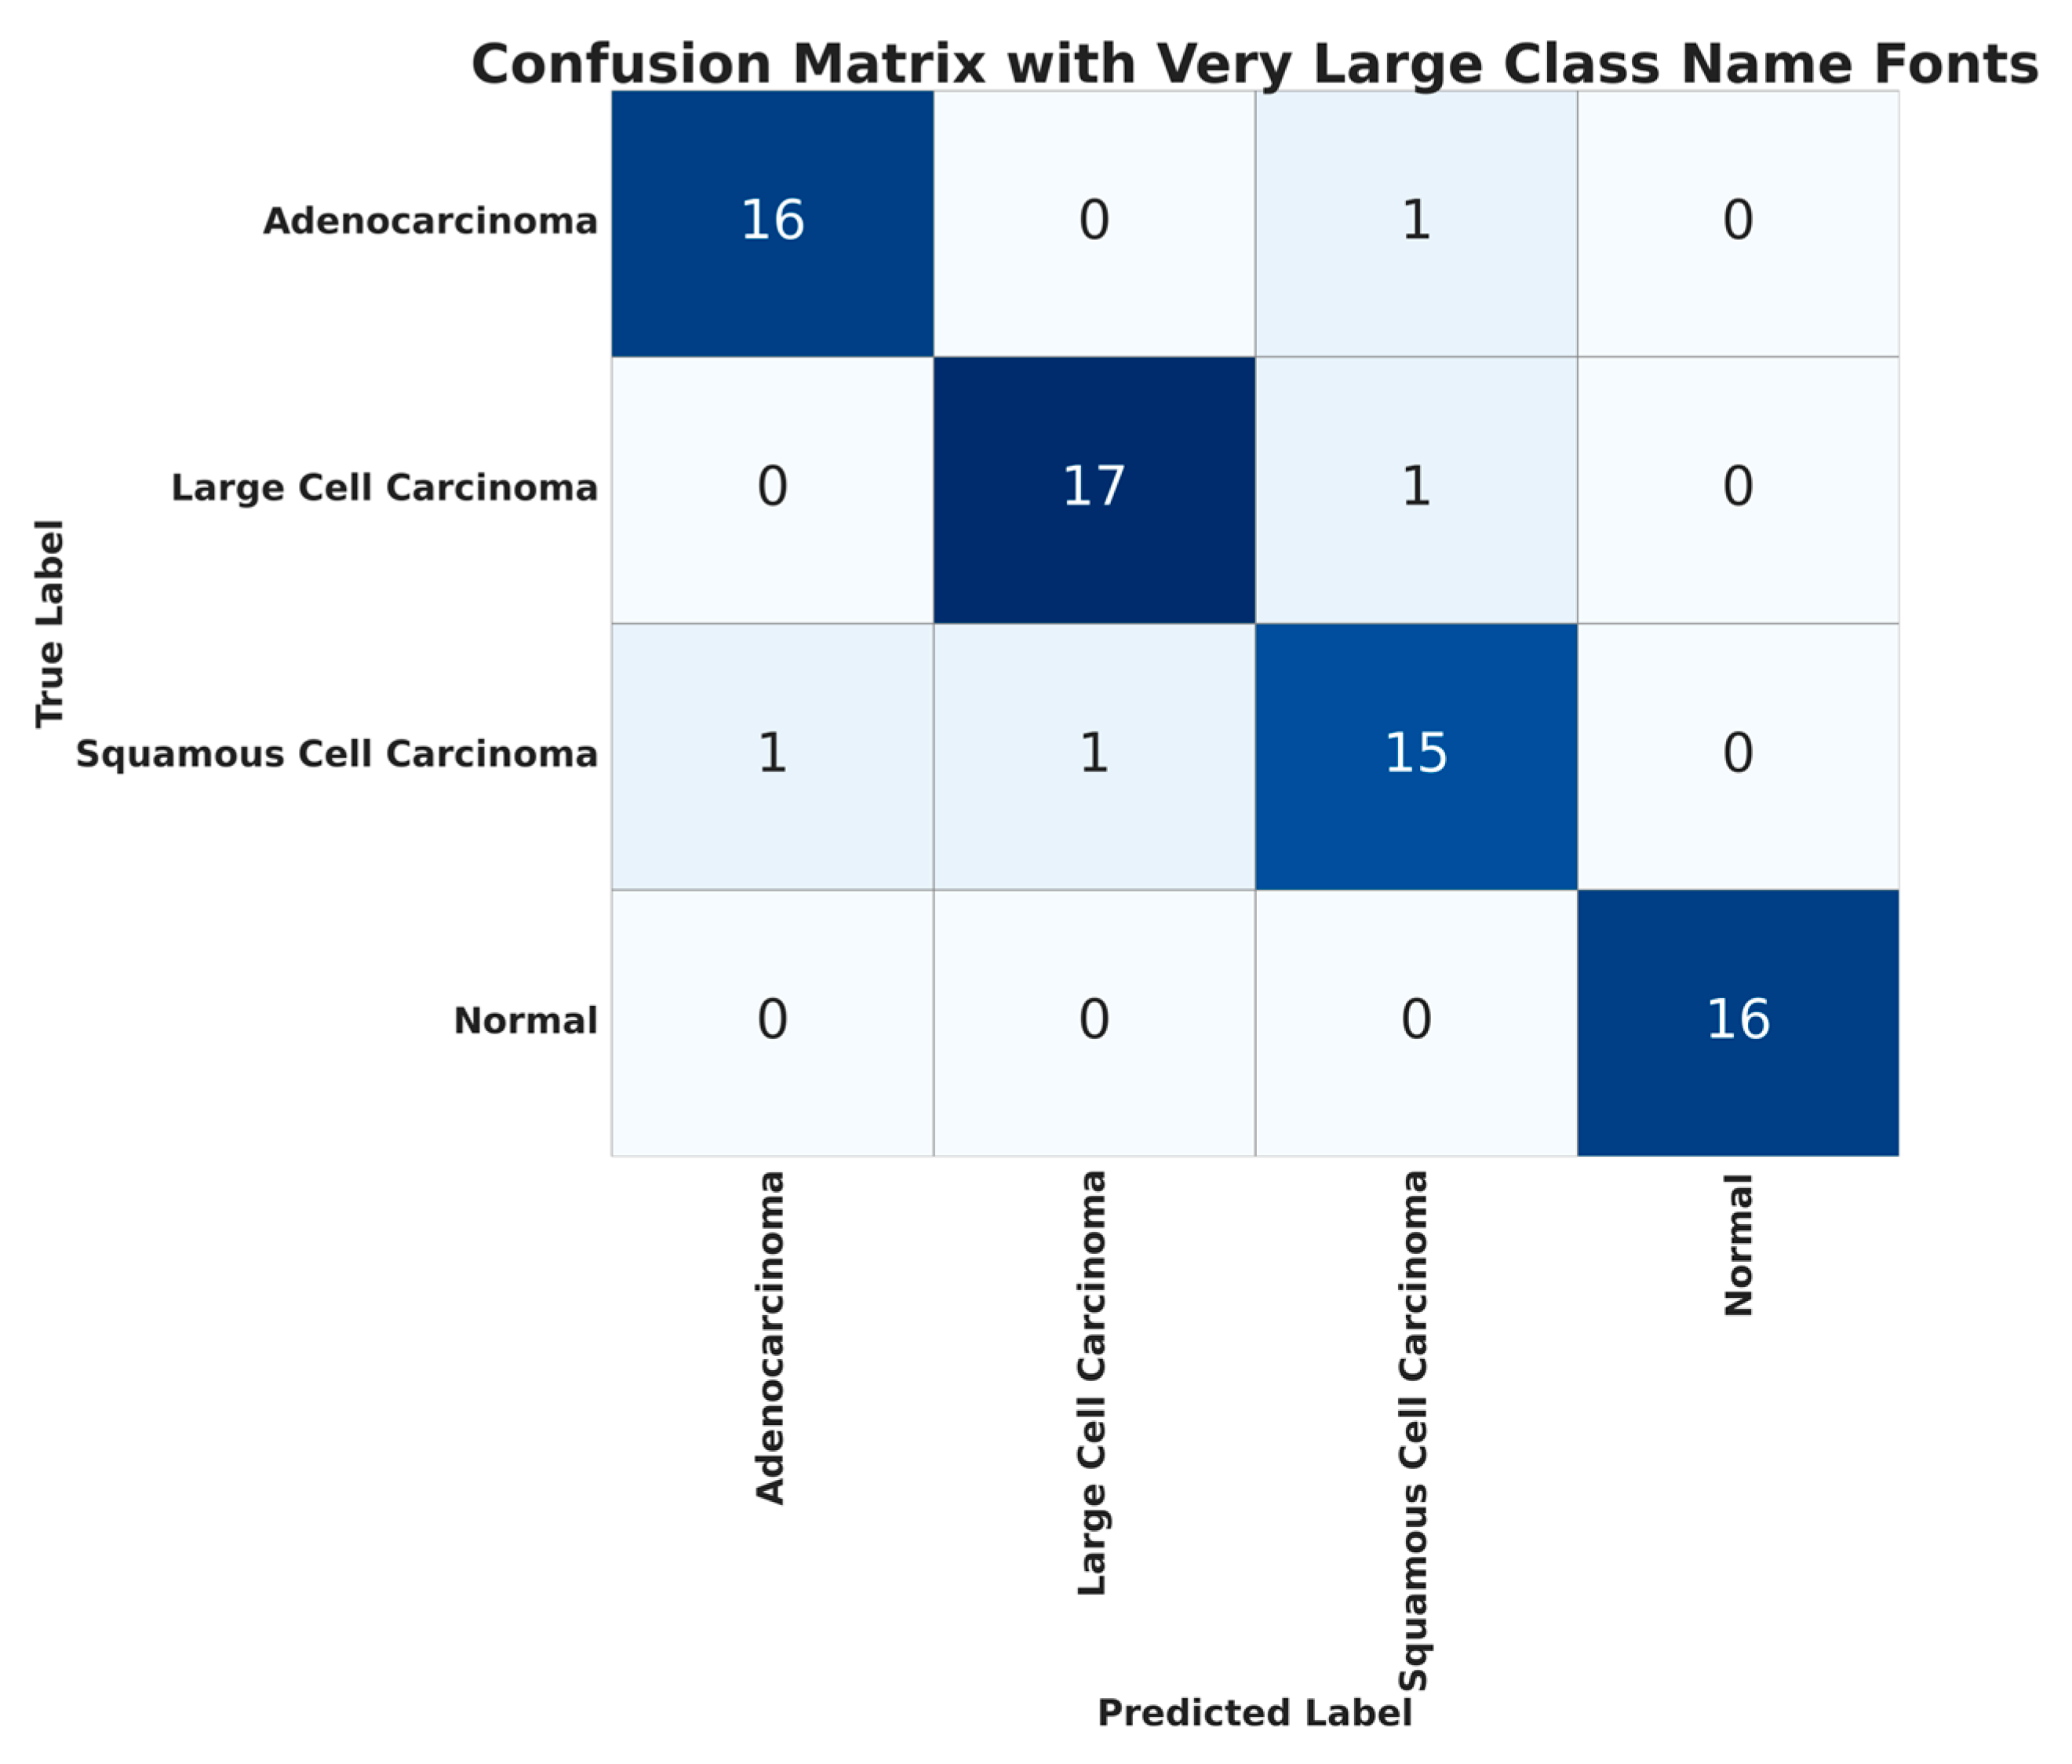

4.3. CT Scan Images

As mentioned in previous sections, the CT scan images used for cancer detection have four classes. The confusion matrix for the classification using ATT-DenseNet is presented in

Figure 9. We do not extensively present the confusion matrices as we did before for histopathological images in order to avoid repetition. Furthermore,

Figure 10 presents an accuracy curve comparison.

We can see from

Figure 10 that the proposed ATT-DenseNet achieves higher accuracy compared to all the baselines by achieving 94% average accuracy on the test set of the data. Similarly, as presented in terms of histopathological images, the F1-score of ATT-DenseNet is found to be higher than all the other baselines for CT scan images. Finally, we compare the proposed method with RestNet in terms of accuracy and the F1-score and see that the proposed method performs better as well.